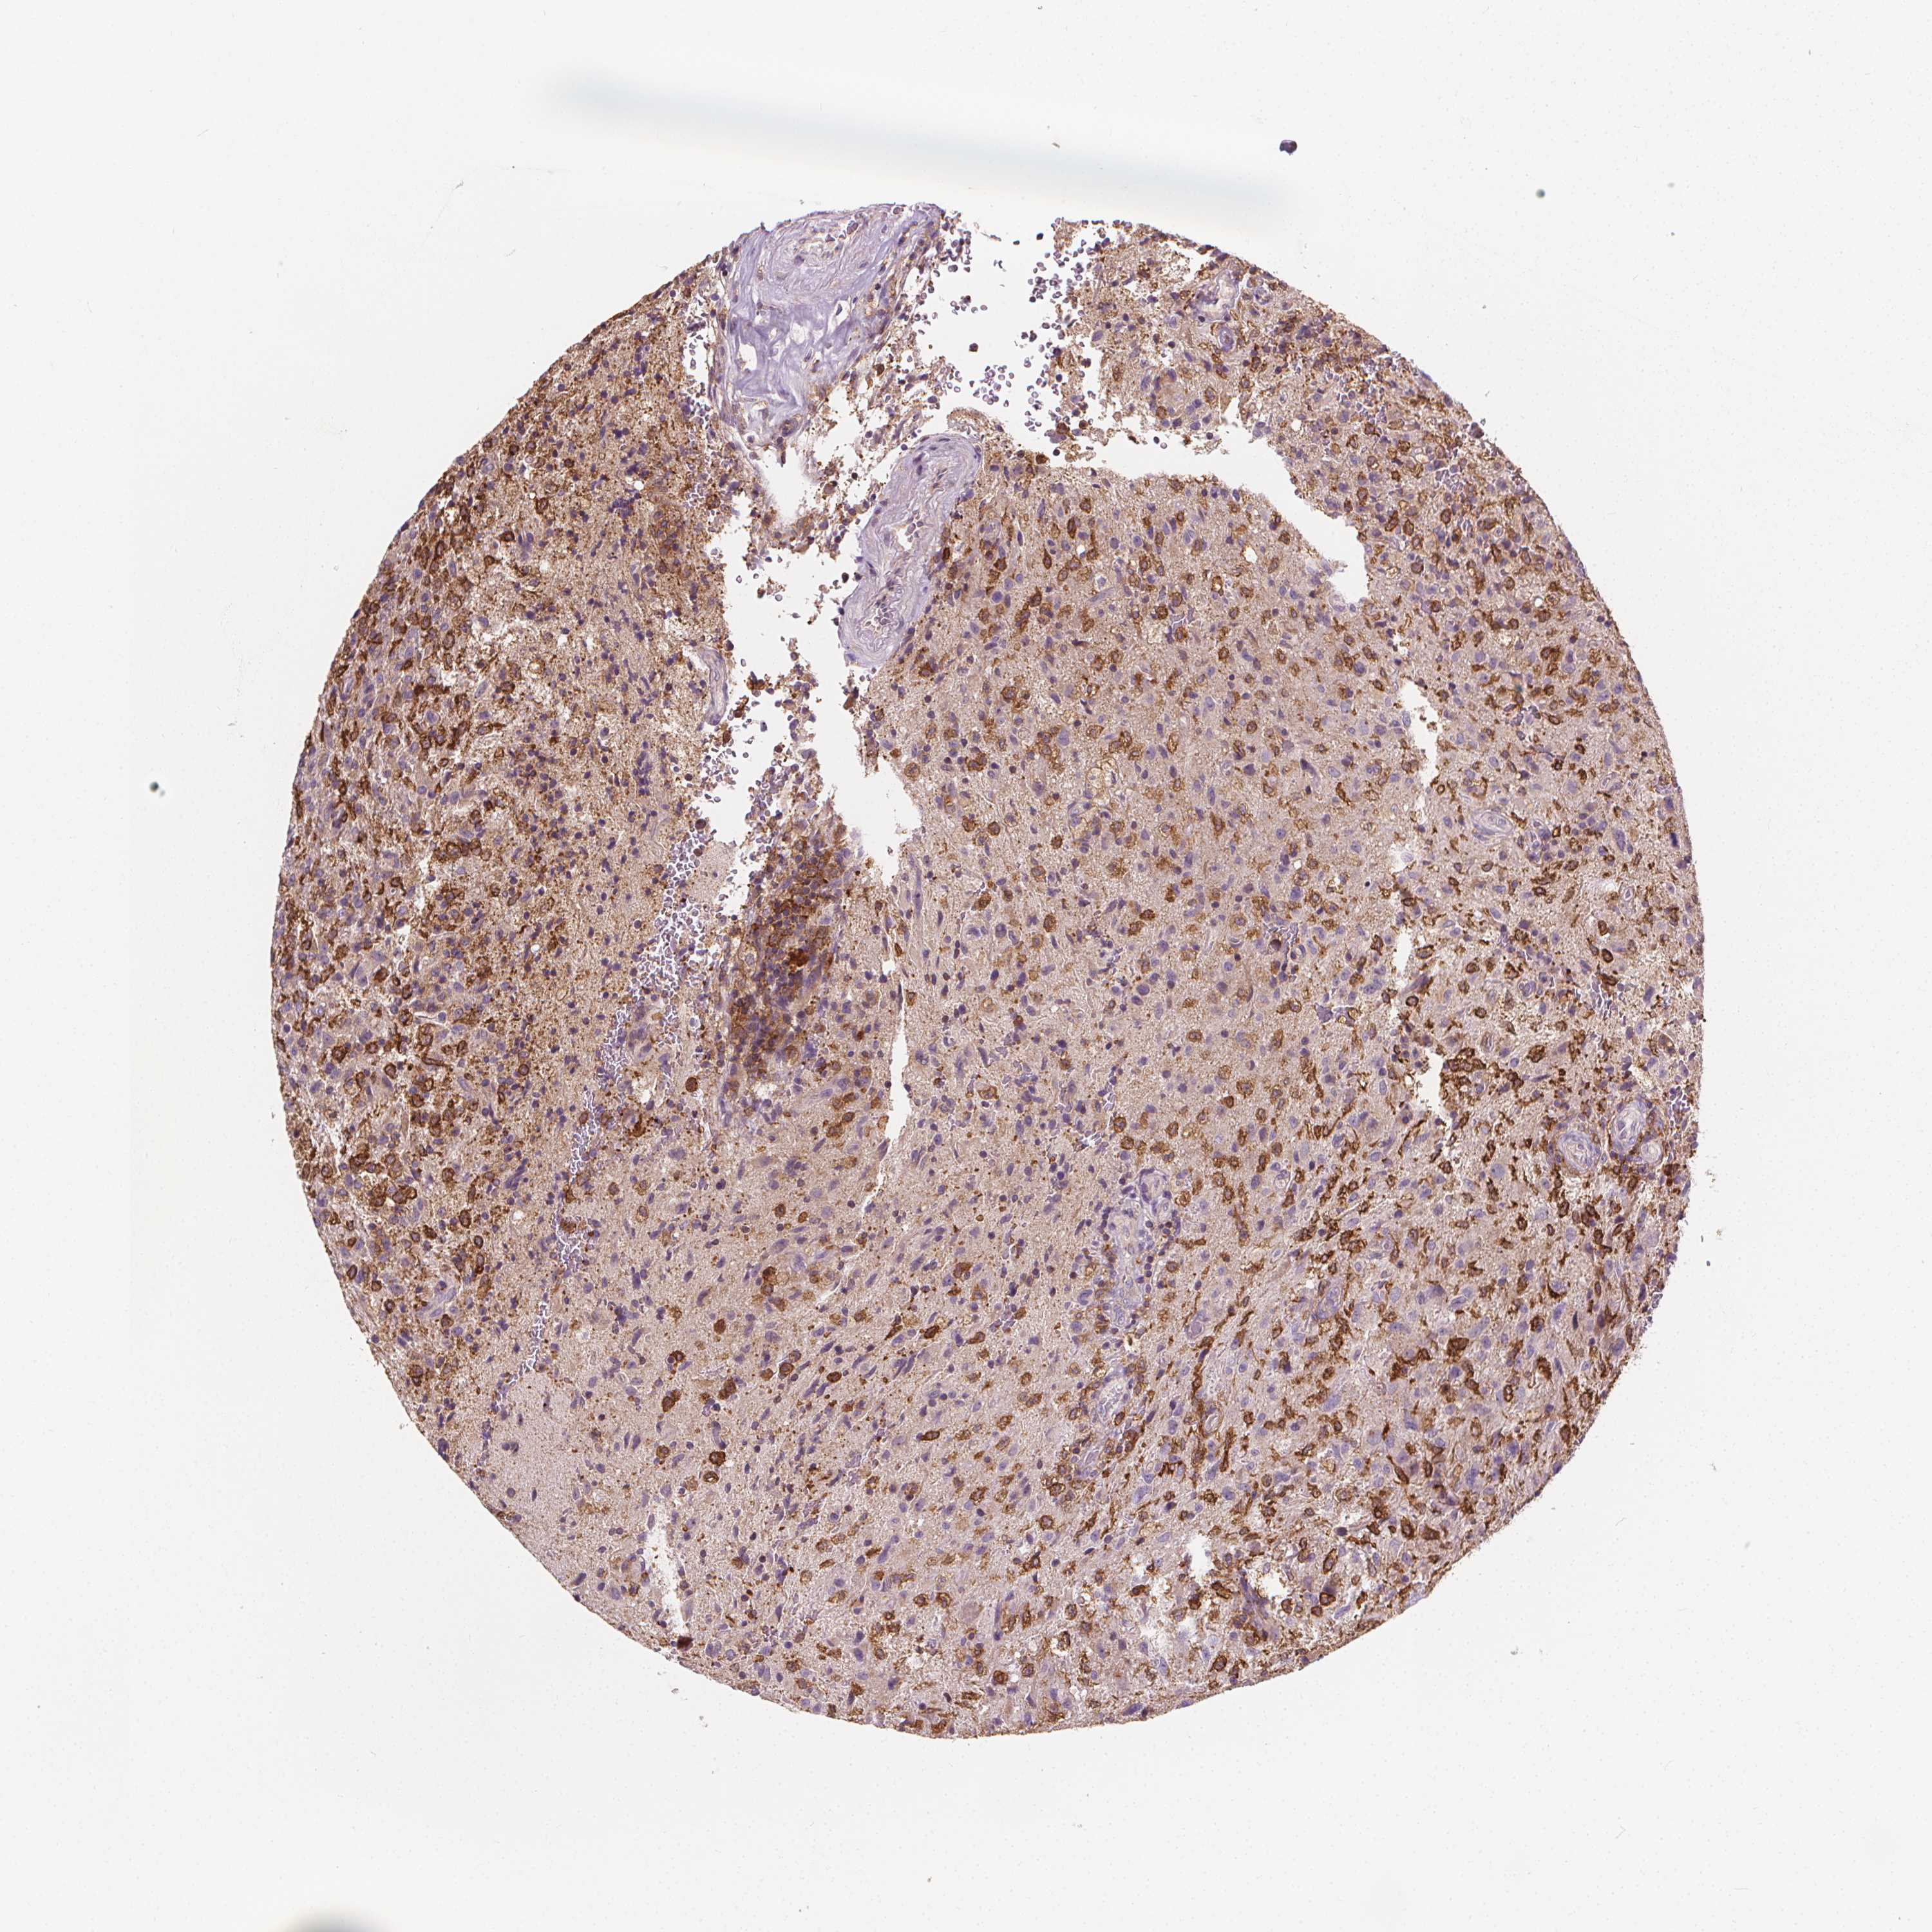

GLIOMA - Protein expressioni

A mouse-over function shows sample information and annotation data. Click on an image to view it in a full screen mode. Samples can be filtered based on level of antibody staining by selecting one or several of the following categories: high, medium, low and not detected. The assay and annotation is described here.

Note that samples used for immunohistochemistry by the Human Protein Atlas do not correspond to samples in the TCGA dataset.

Antibody stainingi

Antibody staining in the annotated cell types in the current human tissue is reported as not detected, low, medium, or high, based on conventional immunohistochemistry profiling in selected tissues. This score is based on the combination of the staining intensity and fraction of stained cells.

Each image is clickable and will lead to virtual microscopy that enables deeper exploration of all samples and also displays staining intensity scores, fraction scores and subcellular localization as well as patient and tissue information for each sample.

Antibody HPA068647

Staining

High

Medium

Low

Not detected

Intensity

Strong

Moderate

Weak

Negative

Quantity

>75%

75%-25%

<25%

None

Location

Nuclear

Cytoplasmic/membranous

Cytoplasmic/membranous,nuclear

Glioma, malignant, Low grade

Glioma, malignant, High grade